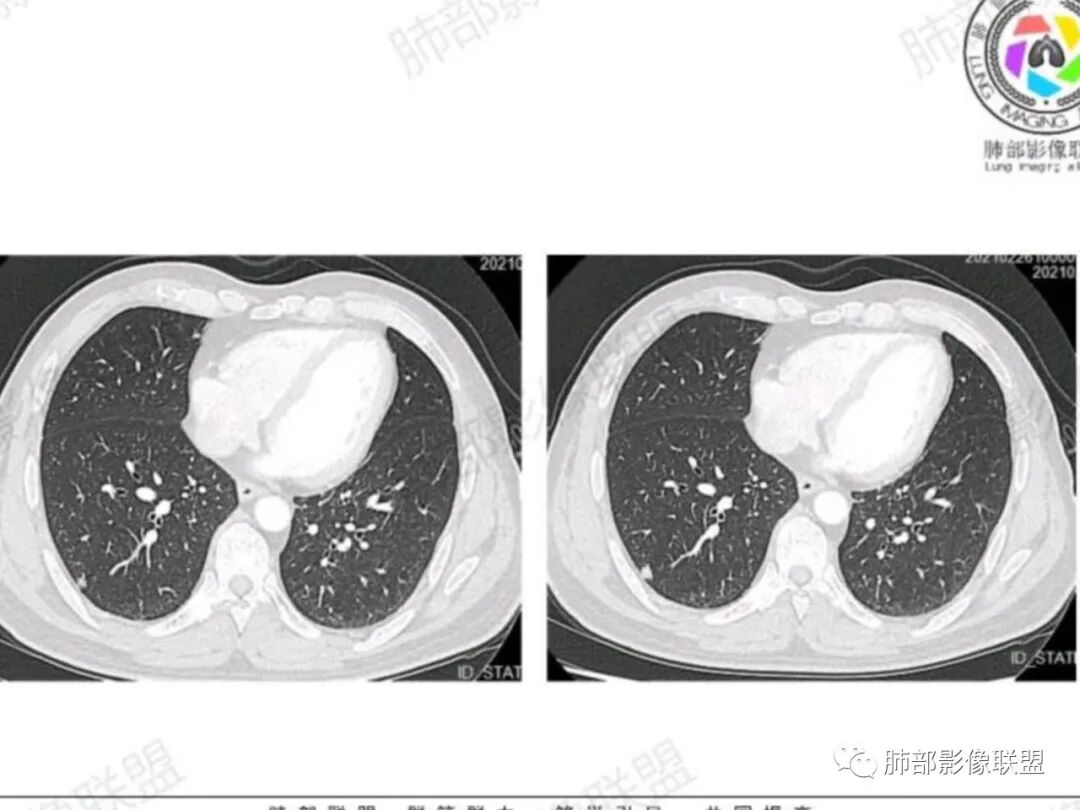

老年男性,右肺下叶胸膜下孤立实性结节,边缘平直凹陷+膨隆,胸膜下脂肪间隙增宽,空洞型胸膜凹陷,中度较均匀强化,与支气管关系不明确。考虑炎性肉芽肿>癌

不过胸膜重建是“圆洞”不是“裂隙”,好像 更多见于良性

男,63,体检发现肺部结节。胸部CT:右肺下叶胸膜下类圆形实性结节影,边界清楚,边缘膨隆、短毛刺,细支气管在病灶边缘截断,小血管进入,胸膜牵拉圆洞样凹陷,胸膜外脂肪间隙增宽。增强密度不均匀,内有点状低密度。引流区域淋巴结增大?考虑恶性,腺?小?鉴别PC、TB等肉芽肿。

右肺下叶胸膜下结节,膨隆为主,细小毛刺,增强静脉期较动脉期变化不大,密度不均匀,体检发现,邻近胸膜有牵拉,重建呈圆洞样改变,良恶性征象都有,老年人,孤立结节,按恶性对待,腺癌或转移瘤>炎性肉芽肿,建议穿刺活检

腺癌>炎性肉芽肿,胸膜表面重建示洞周洞底光整,多见于良性结节,粘液腺癌也可。

右下实性结节,膨隆,有毛刺,强化不甚明显,胸膜下脂肪间隙清,重建空洞样改变,良恶性征象皆有,恶性对待,建议穿刺活检

腺癌,不鉴别(靠肺内侧明显膨隆,毛刺,胸膜侧凹陷,两端与胸膜接触处有微积液,胸膜接触面无增厚,增强中度强化),收缩力相对偏弱,病理类型可能是腺泡为主,也可能是结节型粘液腺癌。

首先,靠肺内侧明显膨隆,毛刺,胸膜侧凹陷,局部胸膜有黏连(不是增厚,是侵润),两端与胸膜接触处有微积液,增强中度强化,就可以基本确定恶性,然后收缩力相对偏弱,胸膜重建洞较圆,病理类型就可能是结节型粘液腺癌。